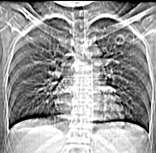

病人为一考上研究生的学生,健康体检发现。请踊跃发表意见。

左肺上叶见后段近侧胸壁见两个薄壁空洞影,洞内无液平,考虑肺囊肿,因为肺囊肿位于肺的外周,囊肿与支气管相通,囊壁薄,囊内无液性成分。以上使我的观点,原与各位交流

左肺上叶尖后段胸膜下可见两个类圆形薄壁空洞,内外壁较光滑,腔内为气体密度,支持结核性薄壁空洞。

我想应是肺囊肿,因为边界清晰,其内无液平面,周边没有卫星灶,还有临床也不支持肺结核

临床无症状,左上肺两枚厚壁空洞,内无气液平面,周围未见卫星灶,囊肿可能大,建议追问病史。请各位老师指正

左飞上叶尖后段两个含气的囊性肿块,边界清晰,其周围未见卫星病灶,考虑肺囊肿.不支持肺结核是因为未见卫星灶,临床未见体征.

左肺上叶后段见两个孤立圆形厚壁空洞,无液平及壁结节。周围清晰,无卫星灶。结合病史,如此大的病灶病人毫无感觉,另外周围如此清晰,应能排除结核空洞;肺囊肿壁应更薄,如合并感染可增厚,但周围应模糊。本人考虑:肺韦格肉芽肿。

左上叶尖后段可见两个中等壁厚空洞,腔内无液平,内外壁光整,局部轻度胸膜增厚,首虑结核。